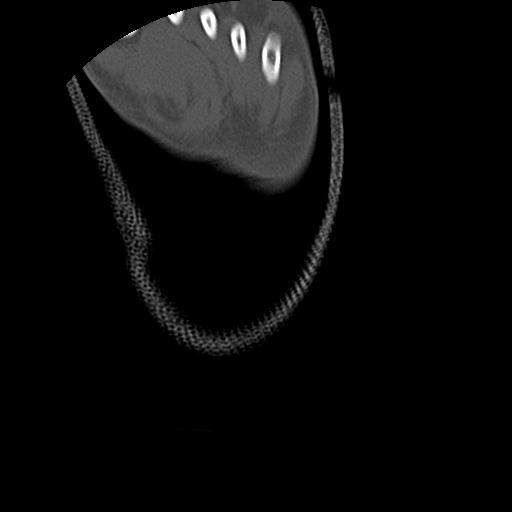

100612 11/25 1/20 右膝 2R 84歳女性 右TKA